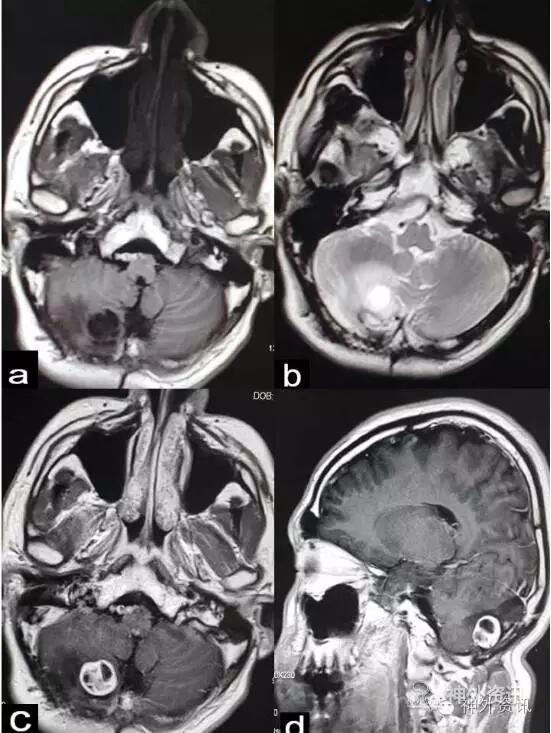

入院后查头颅增强MRI,显示右侧小脑可见类圆形囊实性团块影,边界尚清,直径约18mm,囊性部分呈T1低信号,T2高信号,增强扫描实性部分明显强化;周围可见T2高信号(图3)。

图3. MRI显示右侧小脑可见类圆形囊实性团块影,直径约18mm,增强扫描实性部分明显强化;周围可见T2高信号。